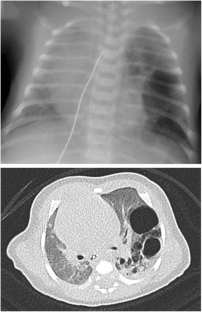

Fig. 2